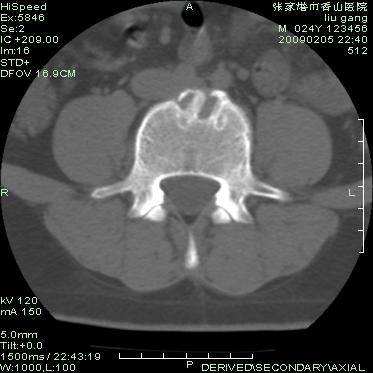

以下是引用随光逐影在2009-3-11 14:43:00的发言:[br]平片:l3、4、5及s1前上缘见类似“切角征”。[br]ct扫描:腰椎多个节段椎间盘向椎体内(椎体前部)突出。